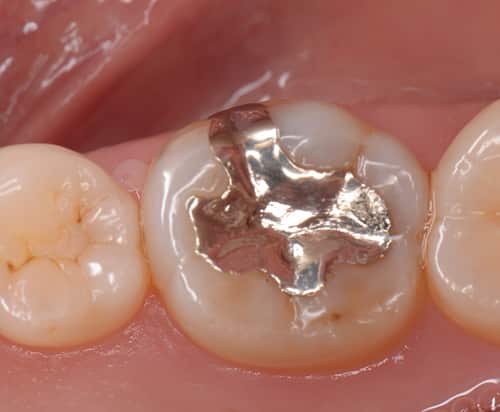

治療写真 術前 パラジウムインレー(銀歯)。10年以上が経過し劣化している。 術後 適合精度の高い(ぴったりと合った)クラウンおよびインレーが装着された。色調も調和している。 パラジウムクラウンを除去し仮歯に置き換えた。5,9 Posts See Instagram photos and videos from '銀歯' hashtag30代女性 銀歯をダイレクトボンディングで白く治療した症例 ご相談内容 笑ったときに銀歯が見えるのが気になっていたそうです。 歯を白くしたい、永く保つようにしたいとのことでご相談くださいました。 診断結果 ご相談のとおり、下の奥歯が銀歯で